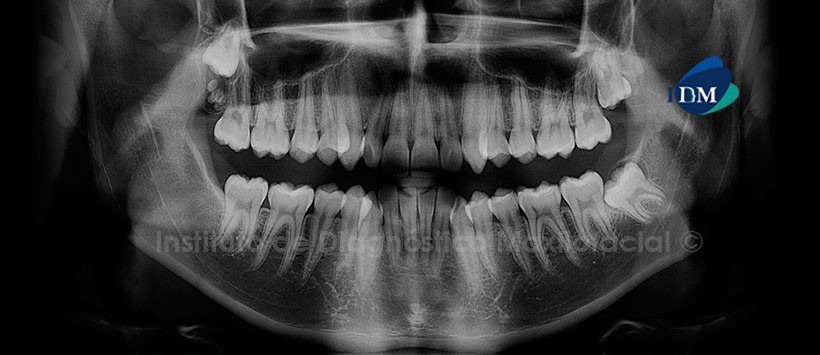

Paciente masculino de 15 años de edad que es referido para la evaluación de los terceros molares. La radiografía panorámica nos muestra la presencia de una imagen de radiodensidad dentaria localizada en la tuberosidad del maxilar superior del lado derecho que ocasiona la retención de la pieza 18. Signos radiográficos compatibles con Odontoma Compuesto. Por otro lado, se aprecian: la pieza 38 mesioangulada e impactada; la dilaceración radicular de la pieza 37 y la ausencia de la pieza 48 (Fig. 1).